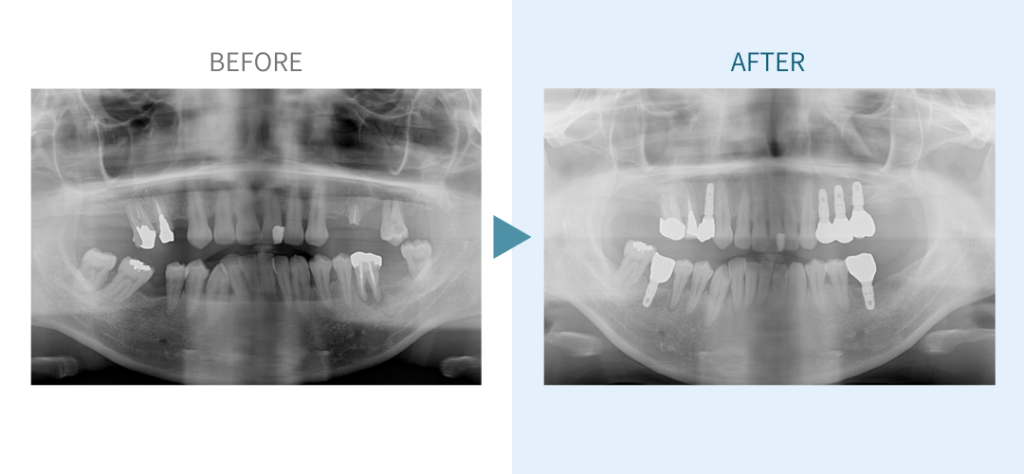

デンタルチームジャパンでは、サイナスリフト(上顎洞底挙上術)や骨造成など、他院で「骨が足りない」と断られた難症例にも対応しています。

こうしたケースは一般的に大学病院以外では難しく、大学で治療を受ける場合は費用が当院の倍以上になることもあります。

私たちは、難症例に関する治療法を学会でも発表しており、その豊富な実績と技術力が評価され、全国から患者様が来院いただいております。

こちらではその一部の症例についてご紹介します。